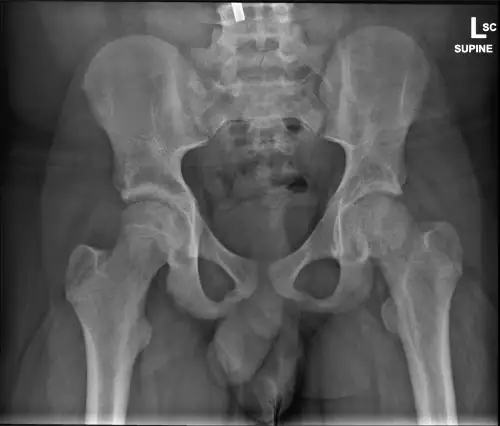

Upon return to the exam room to discuss the results of the tibia and fibula images, the patient’s gait was evaluated. An antalgic gait that favored the left lower extremity was observed, and his left leg and foot were held in external rotation. His antalgic gait in conjunction with the painful passive ROM of the left hip on initial exam led to the decision to obtain AP and lateral left hip radiographs (Figures 1A-1B). These images were reviewed with the on-call radiology resident, and it was suggested to image the bilateral hips for better comparison (Figure 1C). The final images of the bilateral hips were discussed with the on-call radiology resident, as well as the on-call orthopedic resident, to further delineate a possible diagnosis.

The patient’s history, physical exam, and radiographs were concerning for SCFE of the left hip. The urgent care radiographs had poor penetration and were not of the best quality to definitively make the diagnosis. Shared decision making with the urgent care physician, on-call orthopedic resident, and the patient’s mother, came to the conclusion that the patient should present to the pediatric emergency department (PED) at a local tertiary children’s hospital for further evaluation and better imaging.

The PED team repeated radiographs of the bilateral hips (Figure 2) with better penetration that confirmed the diagnosis of SCFE. The orthopedic service was consulted and recommended open reduction and internal fixation to repair the slip in an attempt to prevent avascular necrosis. He was admitted to the hospital under the orthopedic service, made non-weight-bearing status, and ordered nothing by mouth at midnight. He had labs drawn for thyroid stimulating hormone and vitamin D levels that were within normal limits. He was taken to the operating room the next morning and discharged home the same day following the procedure. After the surgery, he had 2 follow-up visits with orthopedics and was doing well.

When there is an appropriate degree of suspicion for SCFE, the next step is to obtain radiographs. Several images are important to aid in the diagnosis including an AP view of the affected hip and the pelvis to compare both sides, as well as a frog-leg lateral view of the affected side. The severity of the slip is related to the stability, chronicity, and degree of slip. A stable slip is defined as a patient that is able to bear weight on the affected limb and walk with or without an assist device—as opposed to an unstable slip, which is defined as a patient who cannot walk in any capacity.[8] Acute versus chronic is defined as the presence of symptoms less than or more than 3 weeks in duration, respectively. Acute-on-chronic is defined as greater than 3 weeks overall with acute worsening of symptoms.4 The degree of the slip is split into 4 categories: pre-slip; mild; moderate; and severe, which can be determined based on the calculated Southwick angle (the angle between the epiphyseal and diaphyseal axes) on the radiographs. Pre-slip occurs when there is a widening of the physis but no displacement of the epiphysis. Mild slips start at <30° of difference between the affected and normal side; moderate is 30°–50°; and severe is >50°.